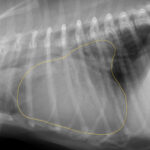

大阪府吹田市・豊中市・箕面市の皆さん。こんにちは。ESSE動物病院の院長 福間です。 今回は、犬と猫の心臓病の患者さんで肺水腫になった子の治療経過を紹介させていただきます。 心臓…